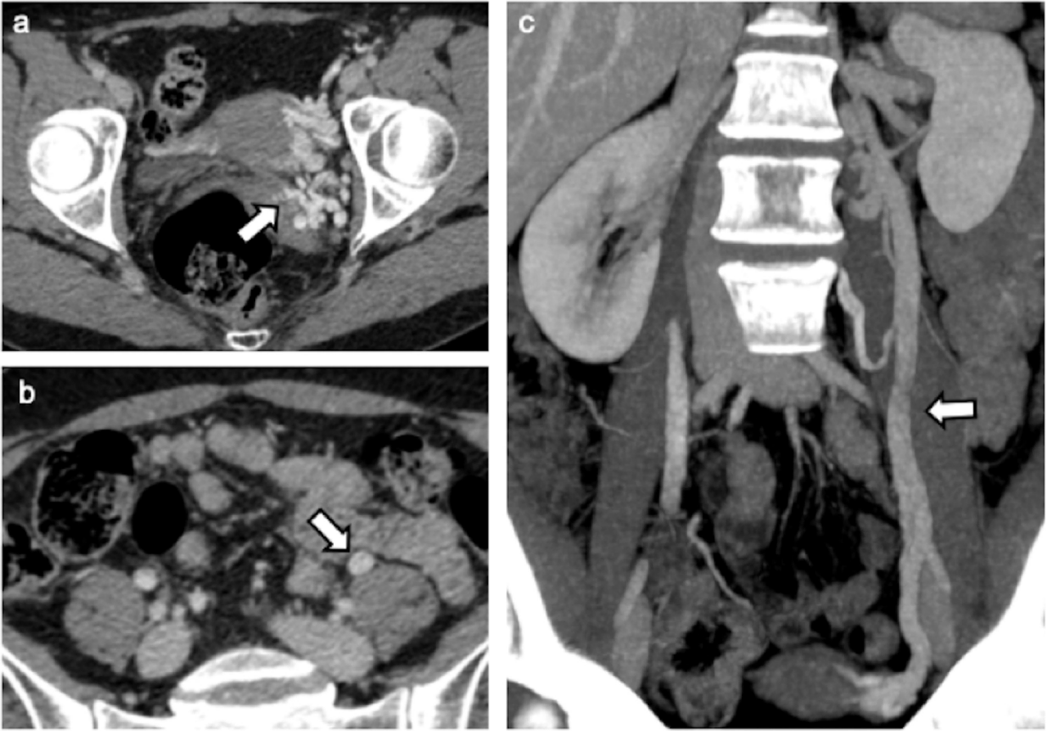

全面评估:CT检查

优势:扫描范围大,结合多平面重建(MPR)和最大密度投影(MIP),能全方位显示下腔静脉、肾静脉、卵巢静脉及盆腔静脉全貌。动脉期左侧卵巢静脉提前显影是其瓣膜功能不全的间接征象。

分级与标准:

反流分级(Hiromura):

Ⅰ级:仅左卵巢静脉反流

Ⅱ级:反流至同侧子宫旁静脉丛,未跨越中线

Ⅲ级:反流至对侧子宫旁静脉丛

直径分级(Szaflarski):

轻度:5-6 mm

中度:6-8 mm

重度:>8 mm(被认为有明确临床意义)

局限:无法做Valsalva动作,可能漏诊隐匿反流;无法直接显示血流方向;平躺体位可能低估静脉扩张程度。

图:CT增强影像显示左侧卵巢静脉II级反流:(a)左侧宫旁静脉扩张(箭头);(b)左卵巢静脉扩张(箭头);(c) MIP重建显示左卵巢静脉扩张(箭头)